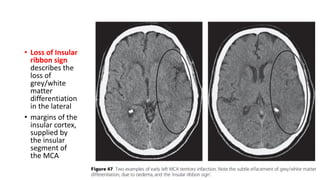

• Loss of Insular

ribbon sign

loss of

matter

in the lateral

insular cortex,

the insular

the MCA

• Loss ofInsular ribbon sign describes the loss of grey/white matter differentiation in the lateral • margins of the insular cortex, supplied by the insular segment of the MCA